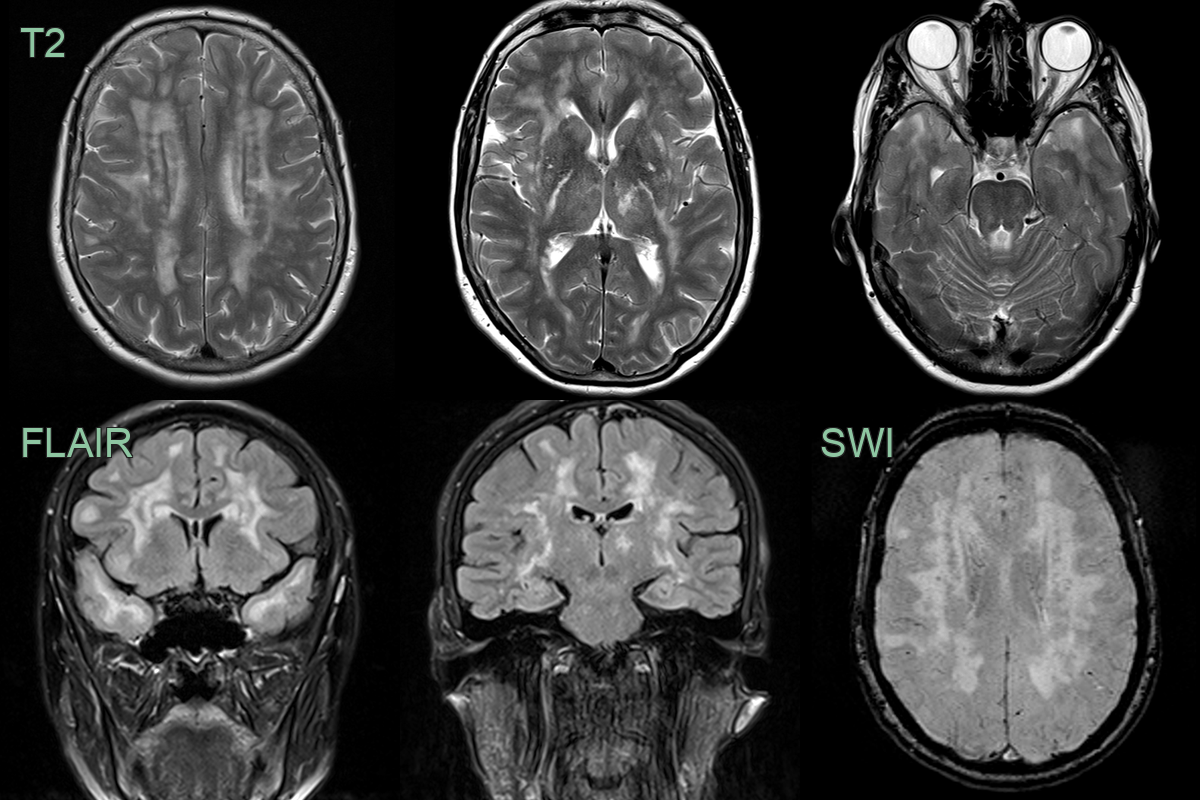

- A 55-year-old patient with a long history migraine presents to the emergency department after developing an aura.

- Patient had an inherited small vessel disease genetic panel that revealed a NOTCH-3 mutation.

Imaging shows a severe burden of small vessel disease that involved the external and internal capsules and the temporal poles, which is not common in conventional small vessel disease. There were a few old lacunar infarcts (e.g., left thalamus) and a small number of microhemorrhages.